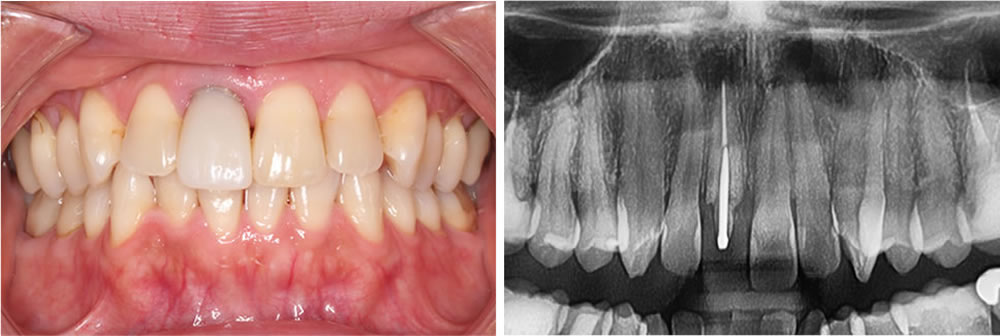

インプラントとセラミック治療で咬み合わせ・見た目を改善した症例 こちらの患者さまは、保存不可能な歯を抜歯後にインプラント治療を行い、古い金属の詰め物や被せ物は、ジルコニアセラミックにて治療する計画を立てました。 術前は、 […]